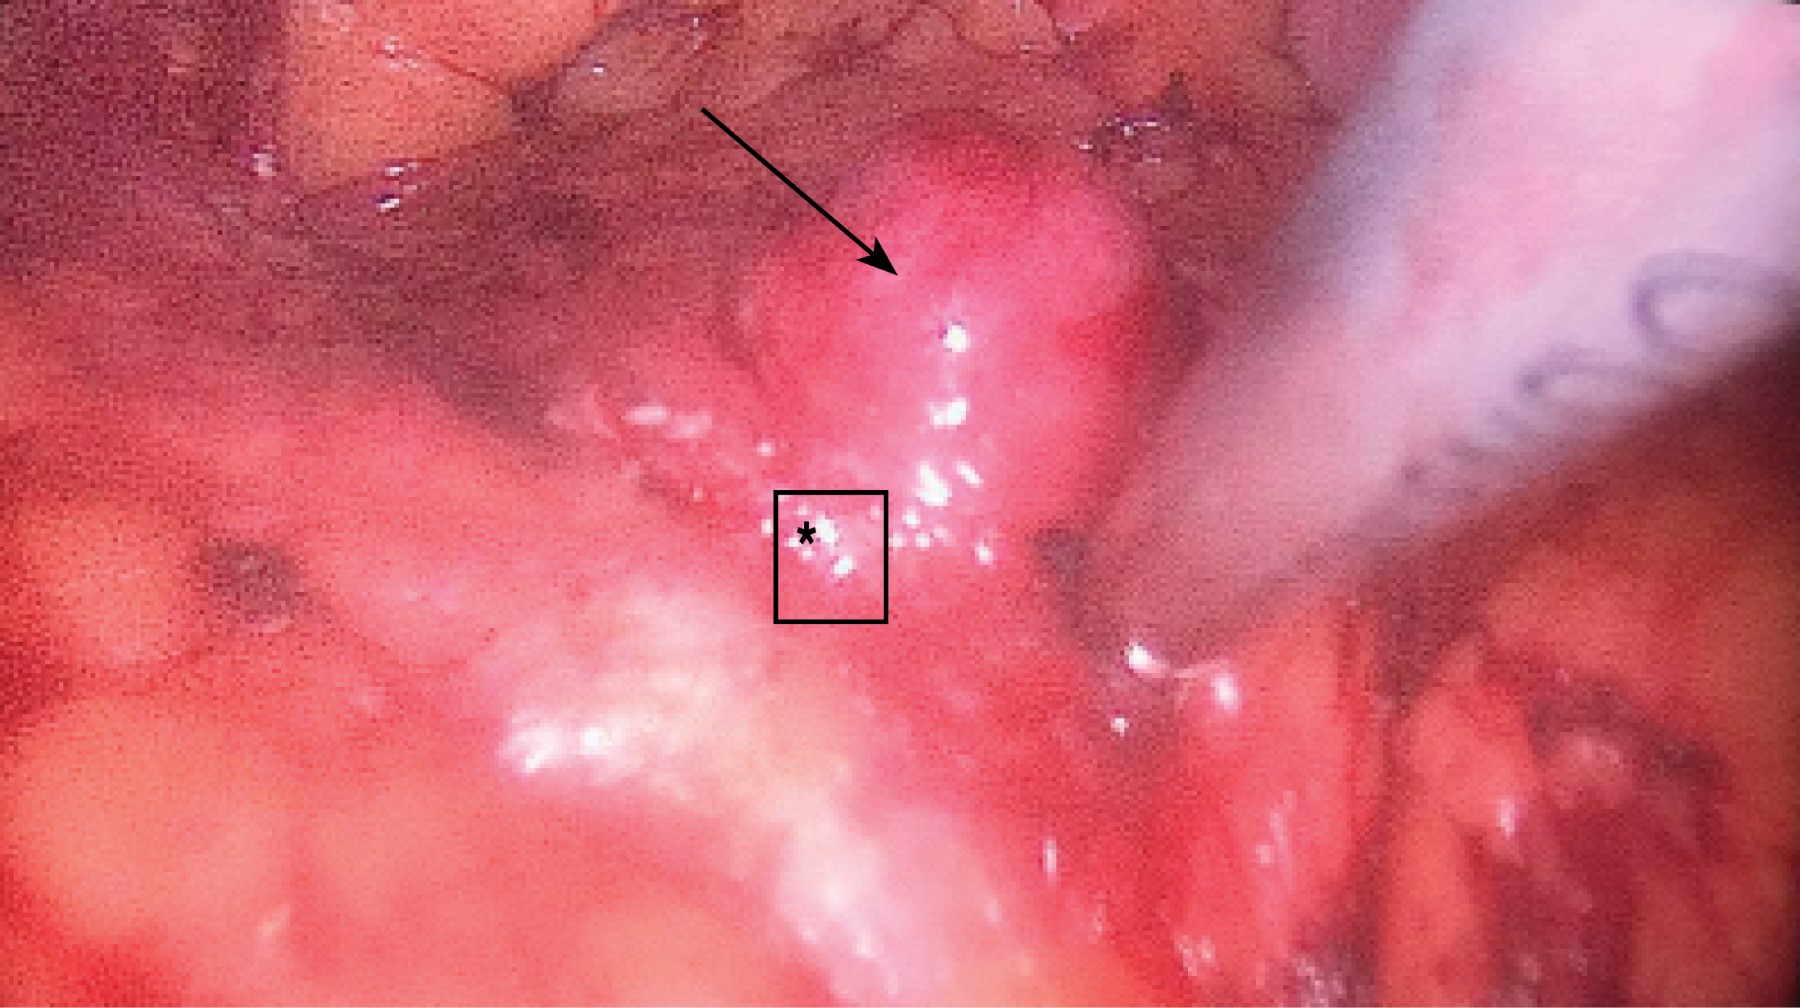

Se trata de un paciente femenino de 51 años de edad sin antecedentes familiares de importancia. Inicia con el padecimiento tres años previos a su ingreso al referir episodios intermitentes de diaforesis, palpitaciones, se valora con glicemia capilar en 28 mg/dl, presenta además cefalea de tipo opresiva de localización frontal, intensidad 5 de 10 en la escala visual análoga, mejora su sintomatología tras la administración de solución intravenosa o alimentos ricos en glucosa. Dos años después se presenta con crisis convulsiva por lo cual acude a valoración, a la exploración física: de edad aparente a la cronológica, tórax sin alteraciones, abdomen globoso a expensas de panículo adiposo, blando depresible no doloroso a la palpación, peristalsis presente y normal, el resto de la exploración sin datos patológicos. Sus estudios paraclínicos muestran hemoglobina glucosada en 4.5%, sulfonilureas en sangre negativas, glicemia de ingreso 37 mg, insulina en 64.1 UI/ml, péptido C en 8.36 ng/ml, TSH 1.8 UI/ml, T4L 1.11 ng/dl, los resultados de la tomografía axial computarizada (TAC) de abdomen contrastado se reportaron normales. En la resonancia magnética nuclear (RMN) aparece una lesión nodular entre la cabeza y el cuerpo del páncreas de 2.0 x 1.8 x 1.6 cm, la cual no condiciona obstrucción. Se procede a realizar ultrasonido endoscópico (Figura 1) corroborando la localización superficial del tumor, se encuentra a más de 2 mm de los vasos esplénicos y del conducto pancreático. Debido al tamaño y localización se procede a realizar enucleación laparoscópica del insulinoma. Se induce neumoperitoneo, se colocan puertos en cicatriz umbilical de 10 mm, otro puerto para el retractor hepático en línea anterior axilar derecha de 10 mm, dos puertos izquierdos y uno derecho de 5 mm. Se continúa con la disección del omento gastrocólico, se levanta la cámara gástrica y se observa la tumoración entre el cuello y cola del páncreas (Figura 2). Se realiza enucleación con bisturí armónico y se extrae de la cavidad abdominal con bolsa por el puerto del ayudante.

Figura 2